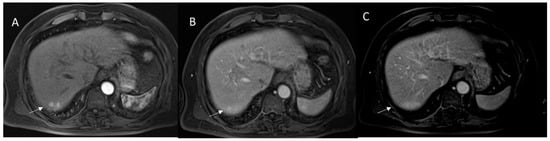

2.4. LI-RADS Treatment Response Algorithm